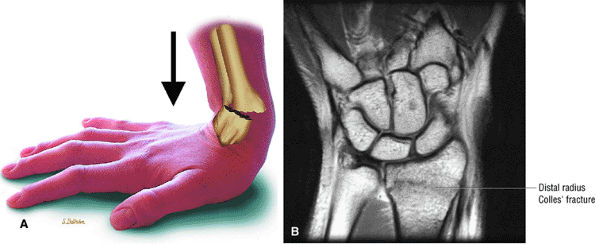

FIGURE 10.18 ● EXTENSOR POLLICIS LONGUS The extensor pollicis longus tendon has a separate tendon sheath throughout its course. It can be injured in Colles' fractures of the distal radius and is sometimes involved in delayed injury following conservative treatment of nondisplaced fractures. This delayed injury is thought to be related to ischemia secondary to edema or hemorrhage compromising the fibro-osseous canal. The extensor pollicis longus extends the distal phalanx of the thumb at the carpometacarpal and interphalangeal joints.